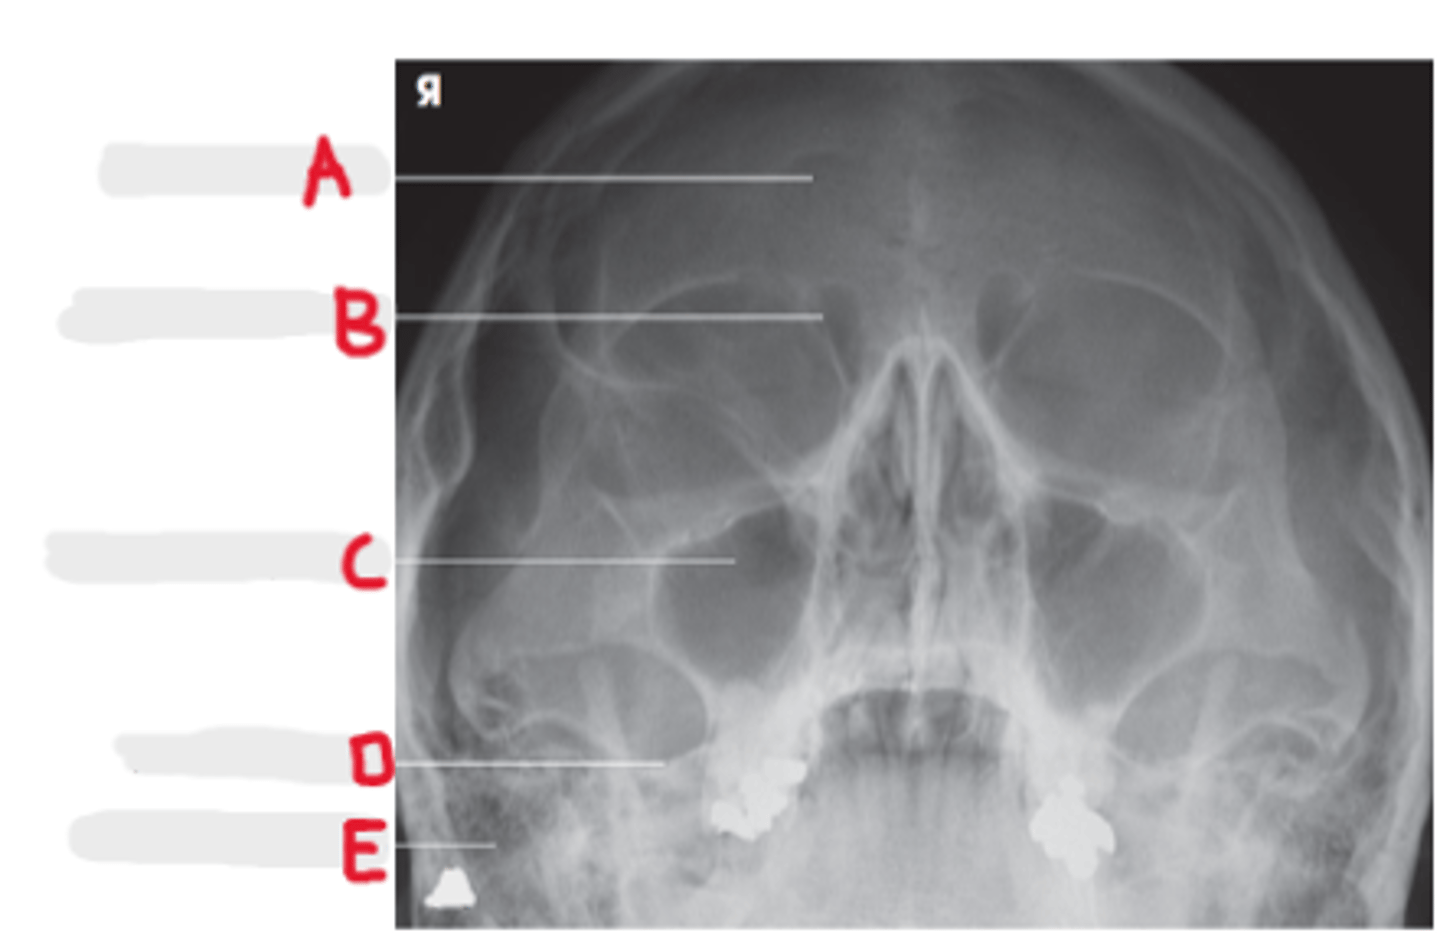

Frontal Sinuses

A

Ethmoid Sinuses

B

Maxillary Sinus

C

Petrous ridge

D

Mastoid air cells

E